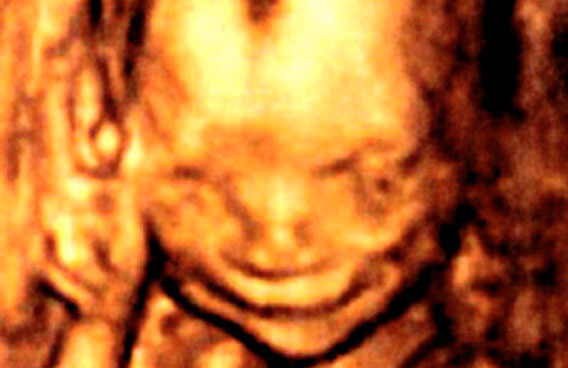

Baby grinning in womb… can’t stop smiling

Joseph in the womb pictured on his 17-week scan. (AGENCY)

Remember the foetus in the womb that appeared to be smiling? Well it is three month’s old now, called Joseph Henry and no surprise, is still smiling. A lot.

According to the Daily Mail Joseph wore an unmistakable grin in a scan taken when his mother was only 17 weeks pregnant.

Professor Stuart Campbell, who took the scan of Joseph, said it was the earliest smile ever recorded on an unborn.